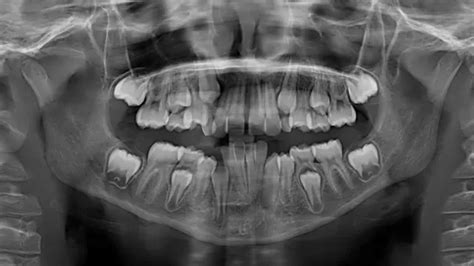

Se detecta por ortopantografía.

Siempre tendrá que ser valorado por el dentista. Lo habitual es que se realice una prueba de imagen como la ortopantografía. Según su sospecha, puede solicitar otras pruebas de imagen. En función de la causa, el especialista decidirá qué actitud terapéutica será la más adecuada: en algunos casos se recomendará mantener el diente de leche y, en otros, se recomendará su extracción.